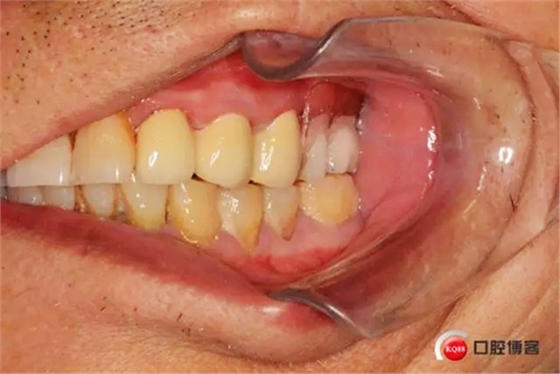

1498574625_742835.jpg

樁核帶入口腔情況

制作完成的義齒,22號(hào)牙前伸合有創(chuàng)傷調(diào)出金屬不影響美觀沒有修復(fù)